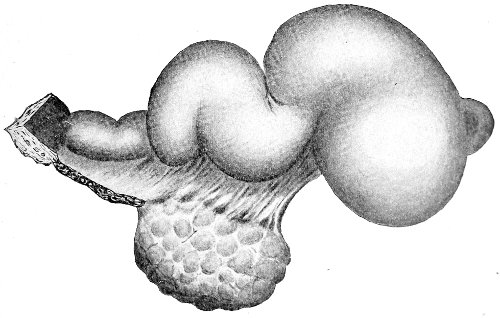

Suppuration of the vulvo-vaginal gland is accompanied by marked swelling and peripheral edema. The swelling may extend to the anus, and is of characteristic shape (Fig. 17). The pain is always severe. Fluctuation is first apparent on the inner surface of the labium majus. If the condition is not treated, one or more fistulous openings appear below the orifice of the duct, and the pus is discharged. The condition then becomes chronic. The fistulous openings persist. Acute inflammation disappears from the gland, leaving it in a condition of hypertrophic induration. A thin, milky or greenish, purulent fluid may be pressed out of the duct or the fistulous openings. Infection from this discharge may be communicated to man, or may ascend the genital 40 tract, producing inflammation of the endometrium or of the Fallopian tubes.

Fig. 17.—Abscess of right vulvo-vaginal gland.

Cysts of the gland may be unilocular if formed at the expense of a single lobule of the gland, or multilocular if several lobules enter into their formation. These cysts may attain the size of the fetal head (Fig. 18).